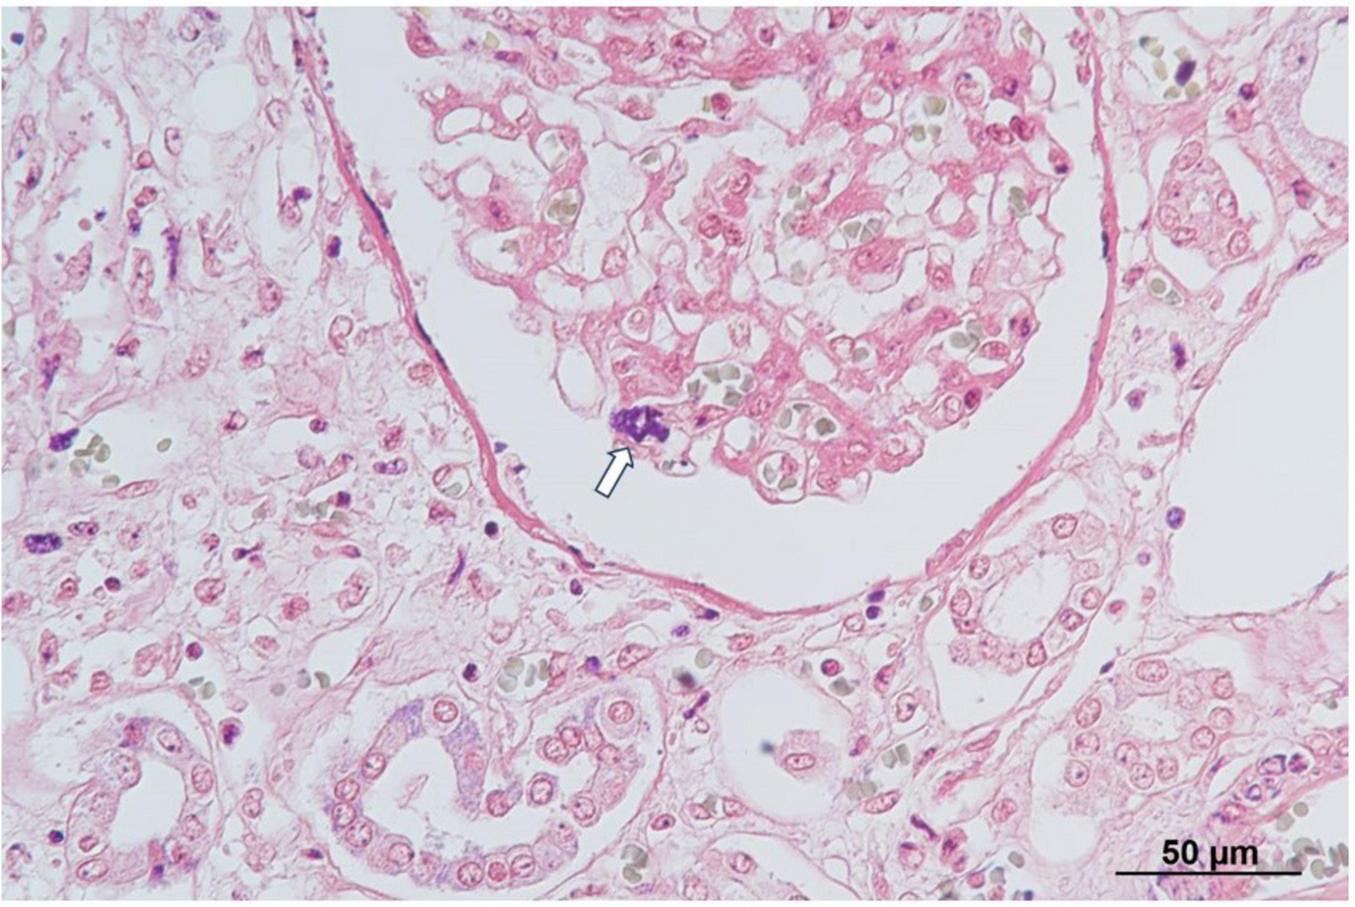

Autopsy imaging using computed tomography (CT) showed enlargement and high density of the left adrenal glands compared to its normal appearance on images taken 5 months prior (Figure 1). Postmortem anatomical examinations revealed the presence of an accumulation of inflammatory cells in the renal pelvis and renal medulla. Despite the absence of bacteriological evidence, the pathology report indicated the presence of pyelonephritis (Figure 2). They also revealed an adrenal hemorrhage and necrosis (Figure 3), with the left adrenal gland showing more severe hemorrhage and necrosis compared to the right. Numerous erythrophagocytic macrophages were observed in the bone marrow (Figure 4), spleen (Figure 5), and liver. Acute splenitis with neutrophil infiltration, indicative of sepsis, was also observed in the spleen (Figure 5). The renal glomerular fibrin thrombus, confirming disseminated intravascular coagulopathy (DIC), was identified (Figure 6). Hemorrhagic diathesis secondary to DIC was evident with intra-alveolar, subpleural, subperitoneal, and ileal mucosal bleeding. The likely source of the E. coli leading to sepsis was identified as pyelonephritis. The autopsy concluded that the cause of death was acute adrenal insufficiency due to BAH and hemophagocytosis associated with sepsis caused by E. coli.

FIGURE 5

Histopathological findings of the spleen. H&E staining reveals neutrophils (black arrows) and erythrophagocytosis by macrophages (white arrow). H&E, hematoxylin and eosin.

Histopathological findings of the kidney. Phosphotungstic acid-hematoxylin staining reveals a fibrin thrombus (arrow) within the glomerular capillary, indicative of disseminated intravascular coagulopathy (DIC).